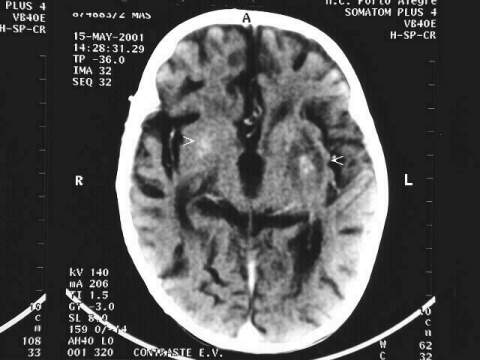

CT scan demonstrating bilateral lesions in the basal nuclei: less dense areas, with central dense areas, compatible with Toxoplasmosis or other parasitic lesions. The one at the left side is larger and more obvious.